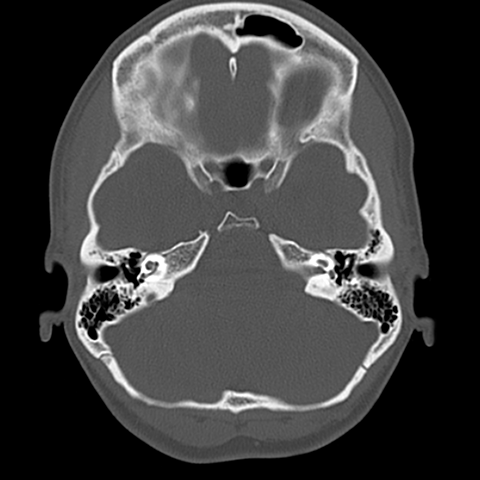

Upper skull base [5 of 7]